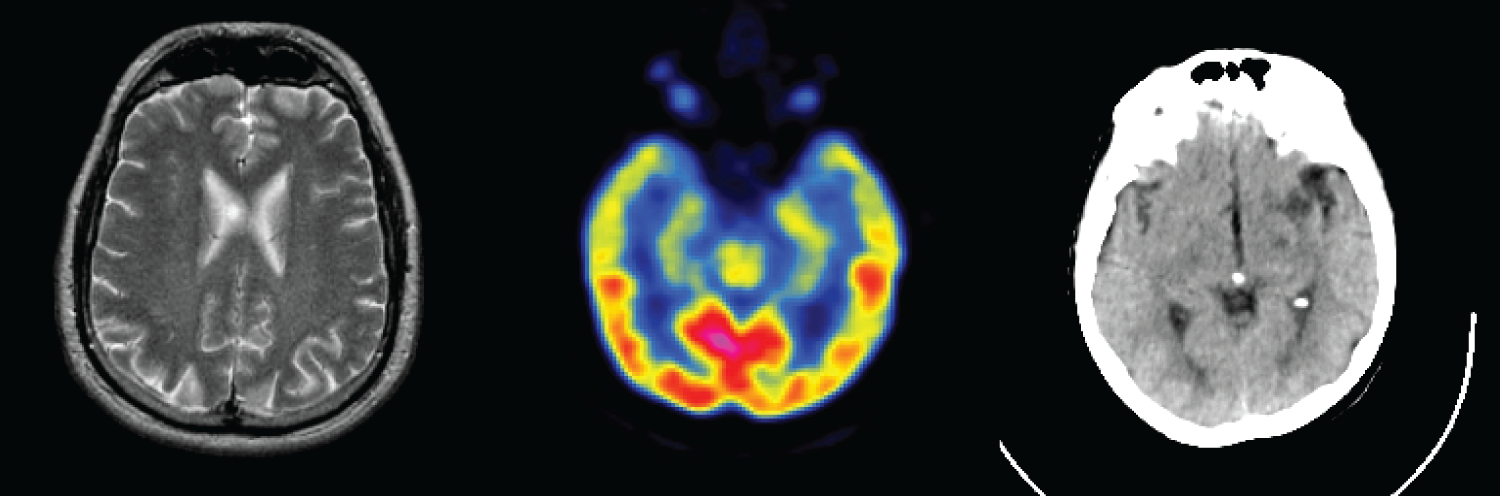

Datasets: To further prove the effectiveness of our proposed fusion method, experiments were carried out on different pairs of brain images (CT-MR/MR-PET). 10000 MRI-PET image pairs as the training set are obtained from the Whole Brain Atlas (http://www.med.harvard.edu/aanlib/ (accessed on 10 July 2025)), and their sizes are 256 × 256. The three medical image categories are shown in Fig. 7. In this paper, 60% of the acquired data are used as the training set, 10% as the test set, and 30% of the data is used as the test set. The fusion experiments results were analyzed with DenseFuse [22], IFCNN [26], NestFuse [27], FusionDN [32] and FusionGAN [35] algorithms.

Figure 7: Multimodal images of the brain